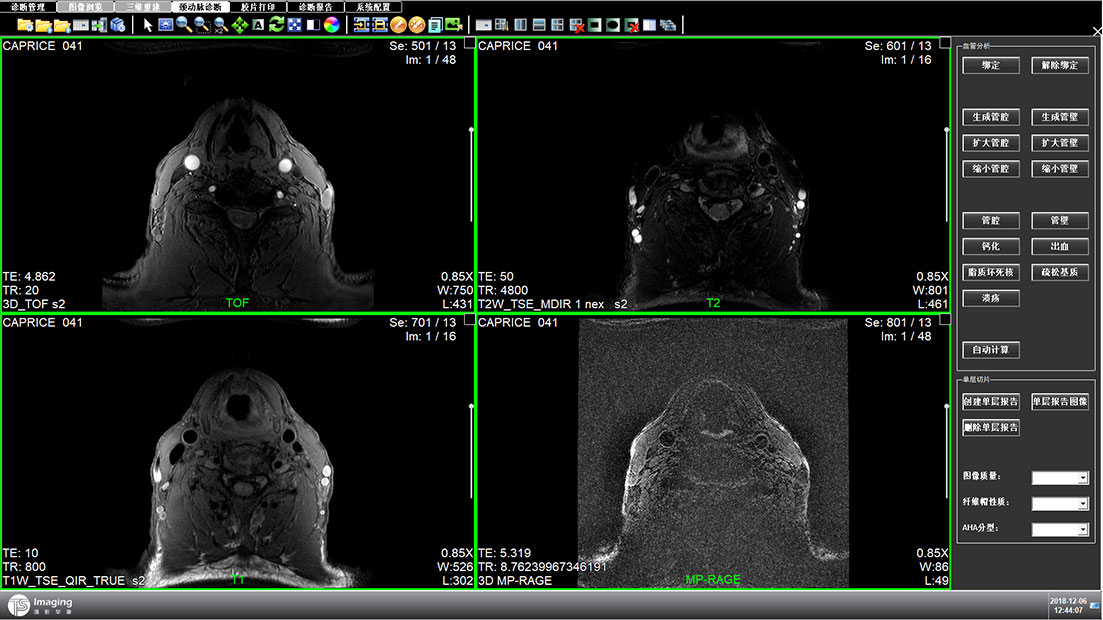

頸動(dòng)脈診斷頁面

頸動(dòng)脈診斷頁面整體布局和三維重建比較相似,最大的區(qū)別是右側(cè)的操作區(qū)域,血管分析都為按鍵操作,通過間隔的大小分成三部分。單層切片除了按鍵還有下拉菜單的操作。